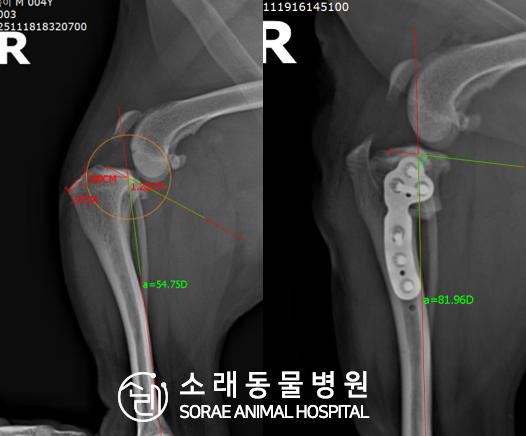

계산식으로 사전에 계획해두었던 플랜에 따라 경골을 절제하고

플레이트와 스크류를 사용하여 임플란트를 적용해 주었습니다.

반대 방향으로 밀려나 어긋나있던 대퇴골과 정강이가

제 자리를 찾으면서 무릎의 각도가 교정된 것을 확인할 수 있습니다